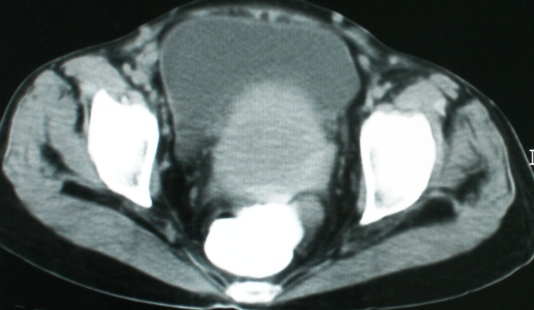

以下是引用zsl6918在2008-11-4 19:14:00的发言:[br]多发转移性改变,子宫改变不除外为原发灶